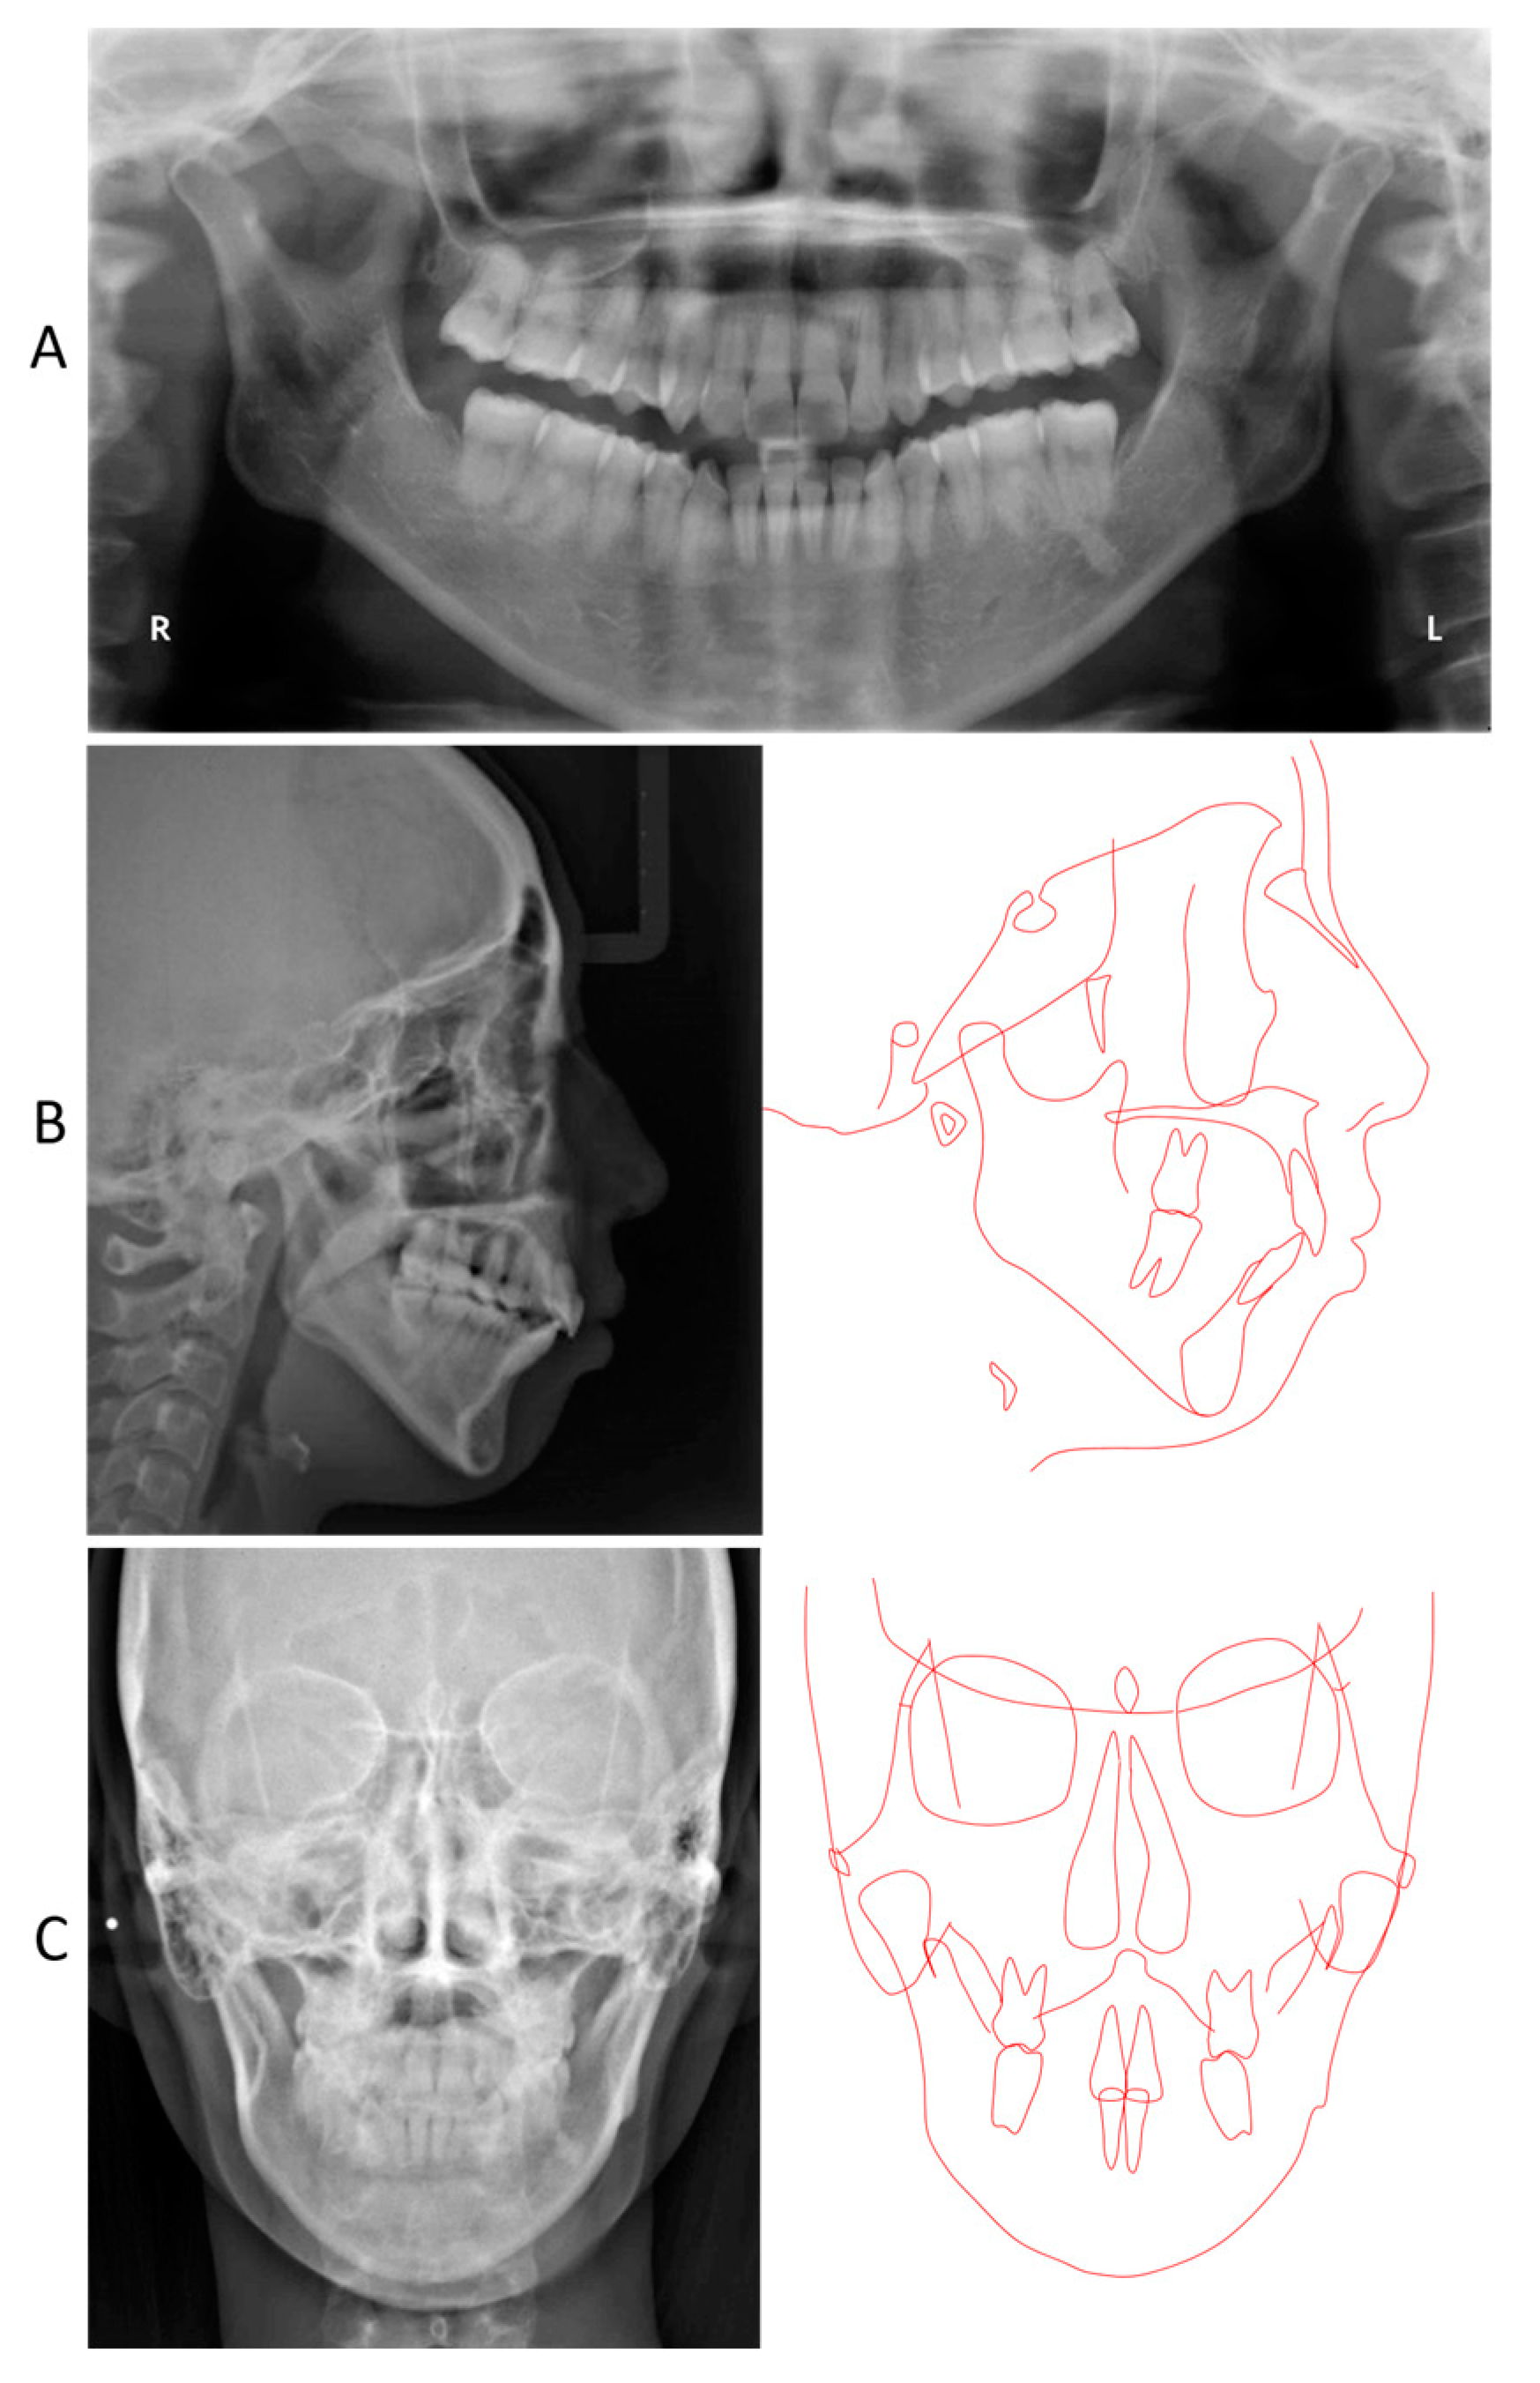

2. Detailed Case Description

2.3. Treatment Progress